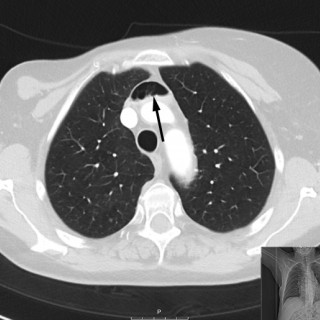

Medisinen i bilder